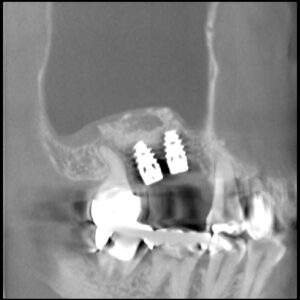

本日無事にアバットと仮歯が入りました この仮歯で食事をしてみて歯周組織との調和を観察します。 インプラントが噛んでいたくない 発音支障がない 歯肉が腫れない 相手のは(対合歯)が痛くない 仮歯の削れ具合 はぎしりがスムーズにできているか などの審査を4週間後に受け そこで ファイナルを…